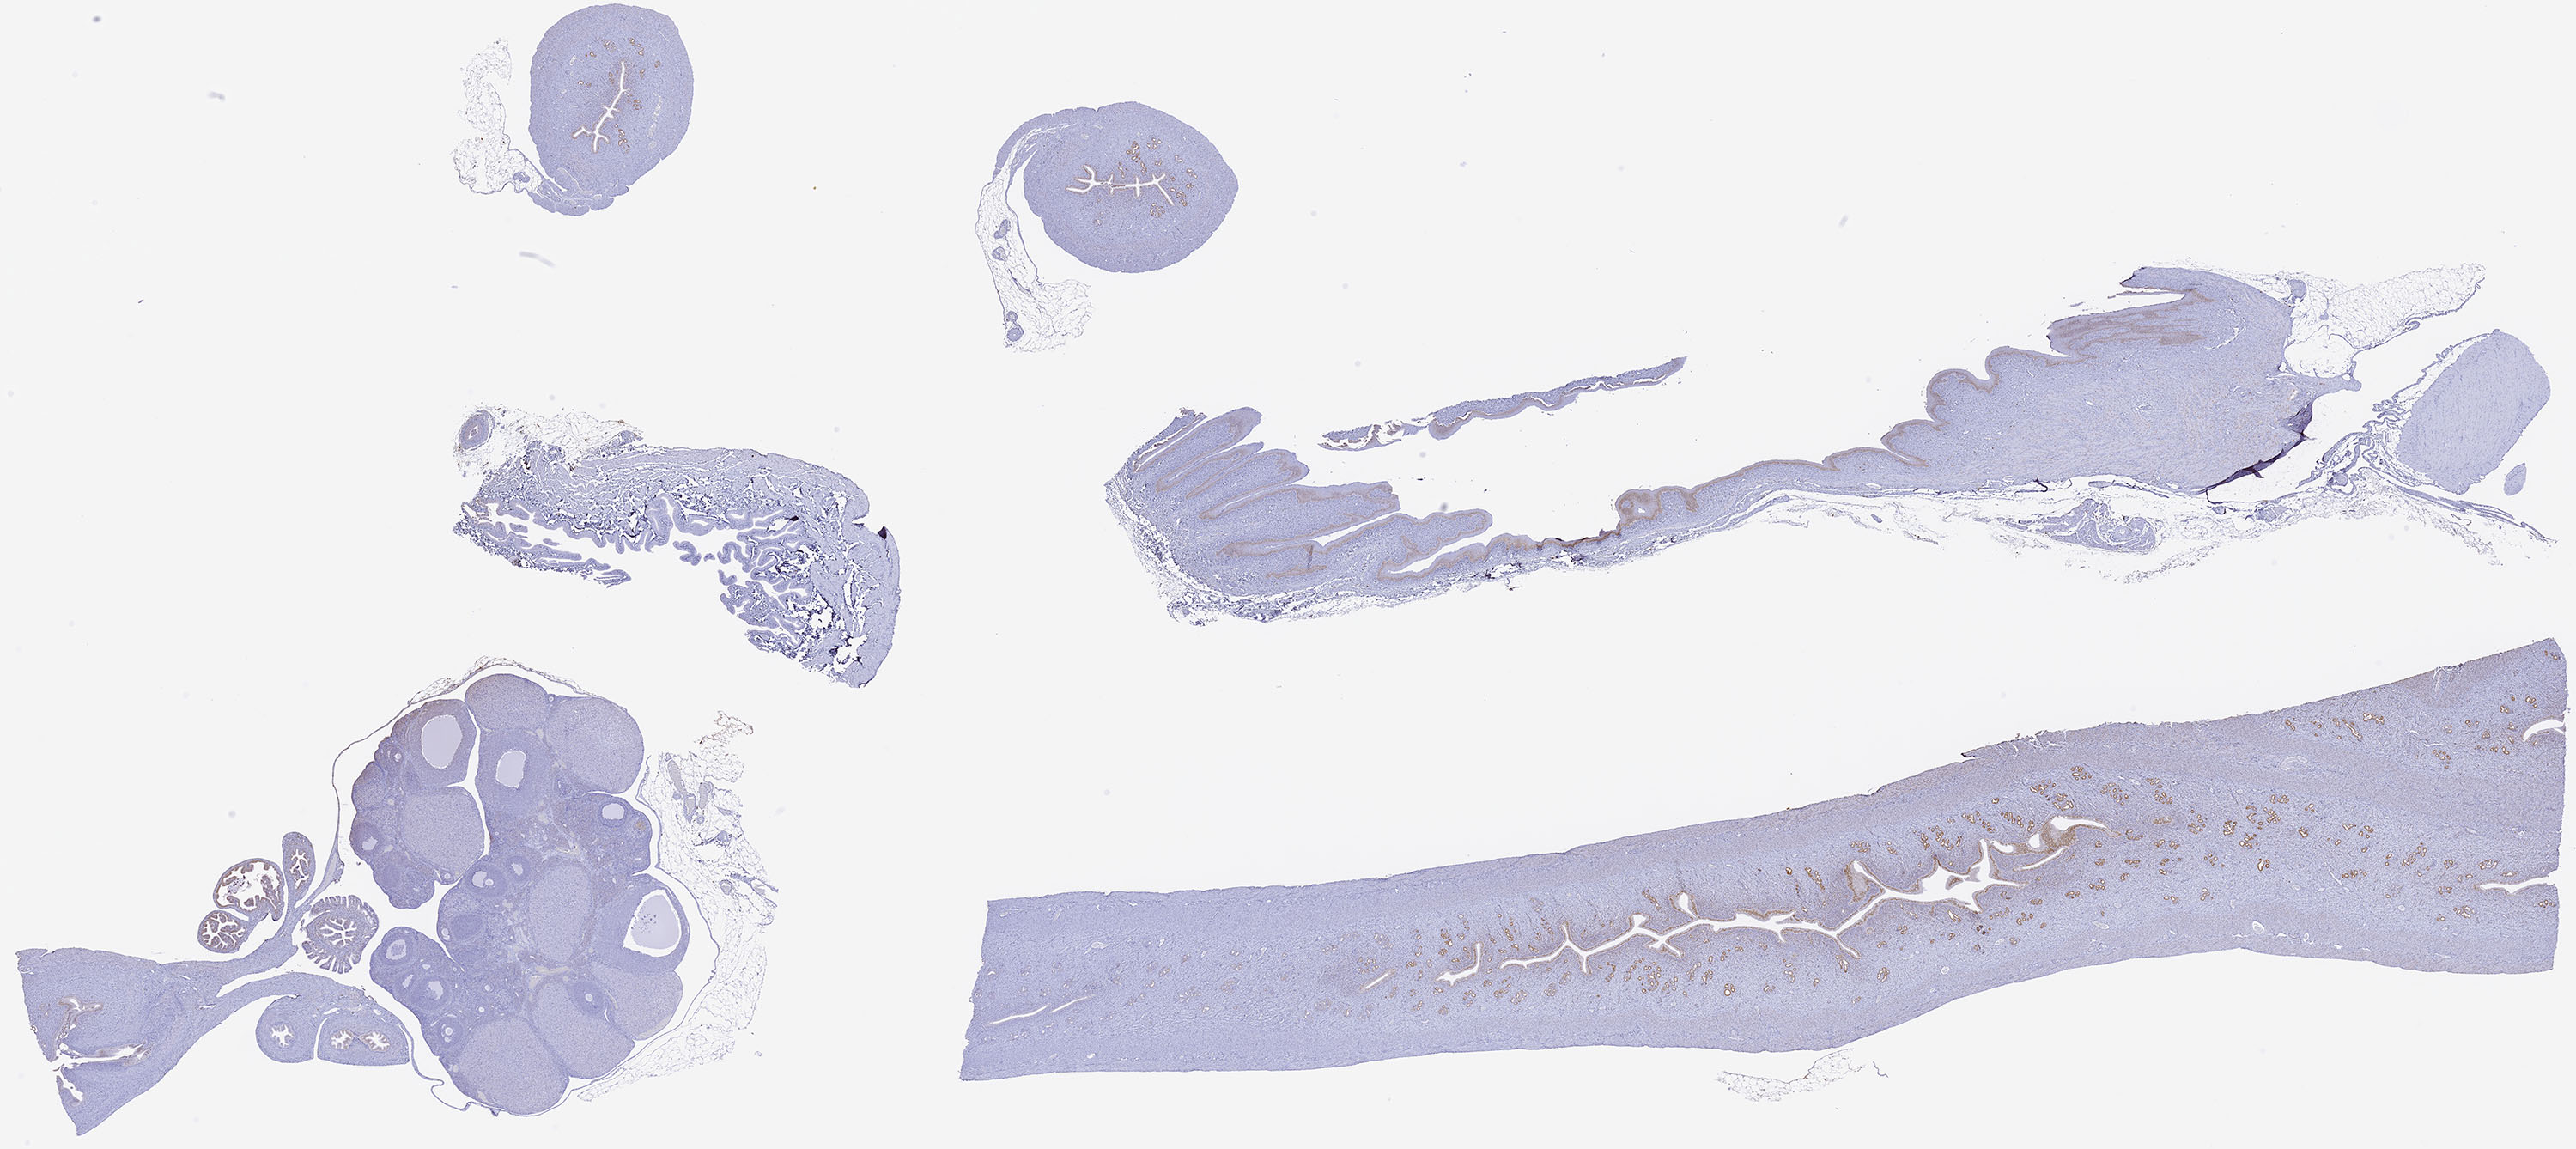

Estrogen Receptor Alpha Estrogen Receptor Alpha: Download a high resolution copy of the Estrogen Receptor Alpha image.